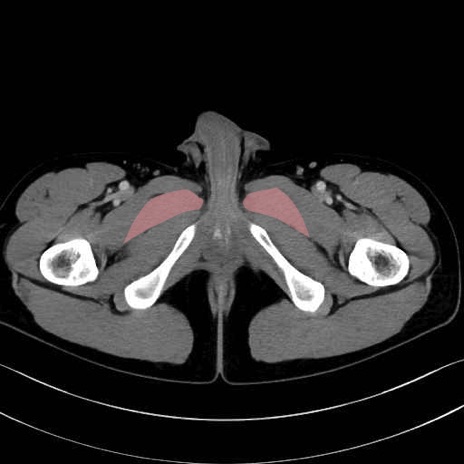

短内転筋(Adductor brevis) のCT画像の解剖

短内転筋 (Adductor brevis)